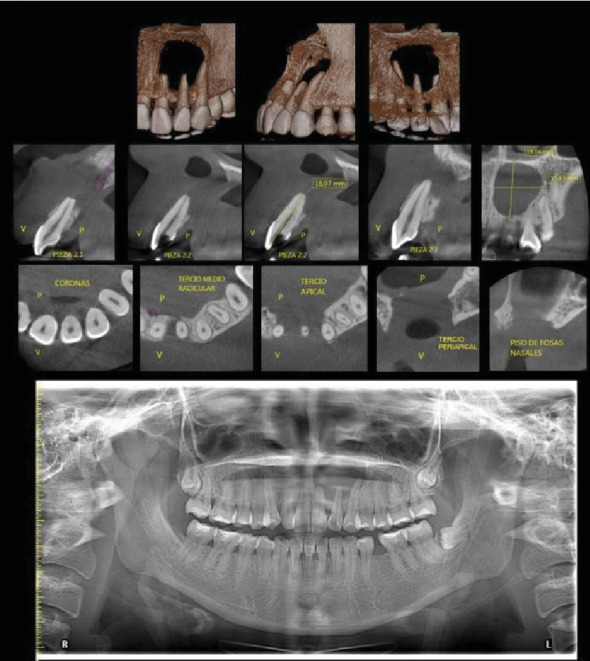

The radicular cyst is an inflammatory pathology affecting the periapical bone tissue associated with teeth exhibiting pulp necrosis. Without timely endodontic intervention, this pathology can lead to significant bone tissue destruction due to its growth pattern, necessitating both endodontic and surgical approaches to halt its progression and remove the involved tissue. This case study details the management of a 23-year-old patient with a history of prior trauma, presenting with pressure in the anterior maxillary region. Tomographic examination revealed a hypodense area involving Teeth 2.1, 2.2, and 2.3. A surgical approach involving enucleation and endodontic treatment was undertaken. The diagnosis was confirmed histopathologically, and follow-up radiographs demonstrated satisfactory bone filling.

根性囊肿是一种影响根尖周围骨组织的炎症性病理,伴有牙髓坏死。如果不及时进行牙髓治疗,由于其生长模式,这种病理会导致严重的骨组织破坏,需要牙髓治疗和手术方法来阻止其进展并切除相关组织。本病例研究详细介绍了一名23岁的患者的治疗方法,该患者有外伤史,表现为上颌前区压力。断层扫描显示低密度区,包括牙齿2.1、2.2和2.3。手术方法包括去核和根管治疗。组织病理学证实诊断,随访x线片显示满意的骨填充。